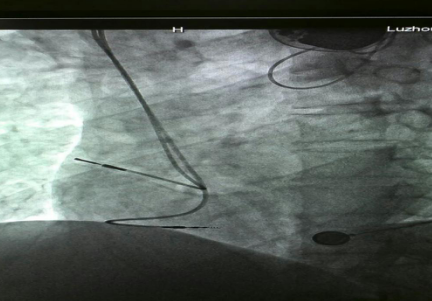

已安裝好的起搏系統(tǒng)

已安裝好的磁共振兼容起搏電極